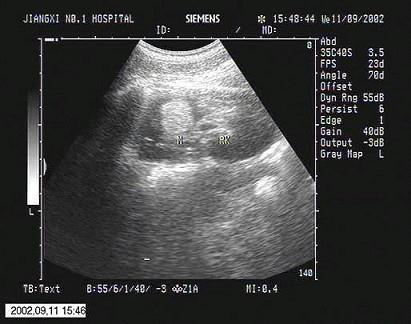

问题 超声检查如图所示,该病例最可能诊断?(?)

选项 A.肥大肾柱 B.肾脏局灶性炎症 C.肾脏肿瘤 D.肾脏错构瘤 E.肾脏脂肪瘤

答案 D